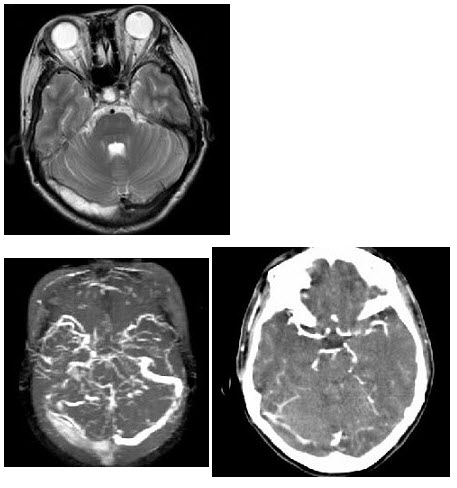

女,37岁,产后10天出现剧烈头痛头昏伴神志不清2天,请根据所提供图像,选择最可能的诊断()

A . 右侧蛛网膜下隙出血

B . 右侧脑膜脑炎

C . 右侧硬膜下血肿

D . 右侧脑梗死

E . 右侧静脉窦血栓形成

女,37岁,产后10天,出现剧烈头痛头昏伴神志不清2天,根据所提供图像,最可能的

[单选题]女,37岁,产后10天,出现剧烈头痛头昏伴神志不清2天,根据所提供图像,最可能的诊断是()A . 右侧蛛网膜下腔出血B . 右侧脑膜脑炎C . 右侧硬膜下血肿D . 右侧脑梗死E . 右侧静脉窦血栓形成